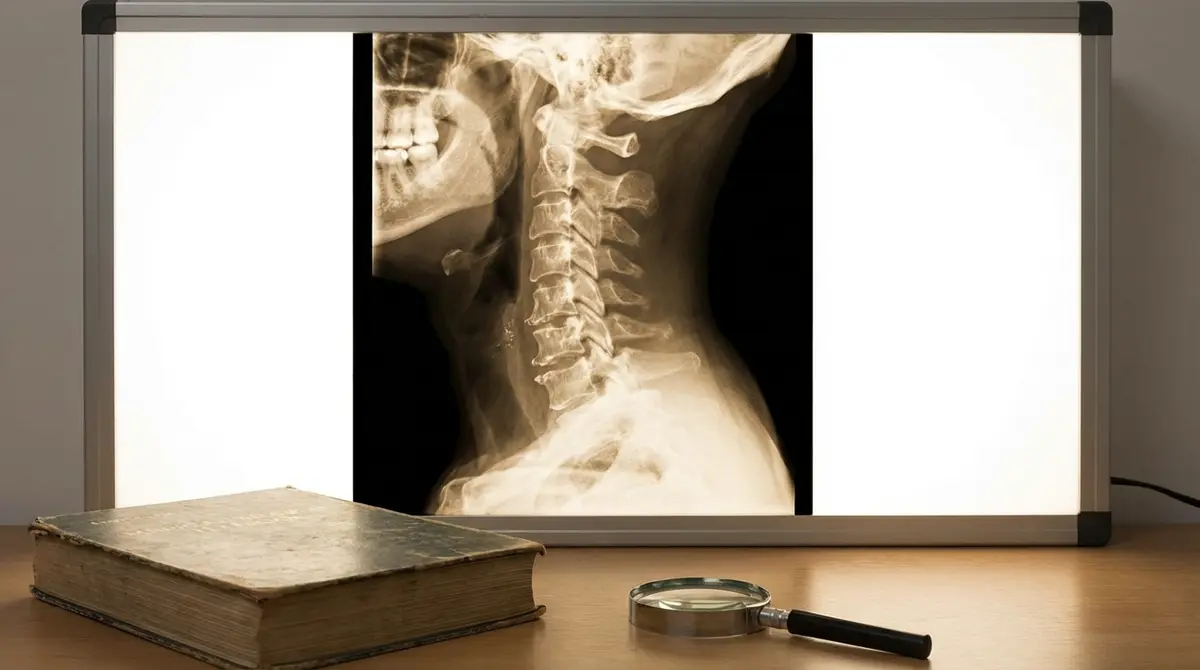

O desgaste natural dos discos entre as vértebras do pescoço (C3 a C7). Com o tempo, o disco perde água (desidrata), fica mais baixo (perde altura), e pode formar osteófitos (bicos de papagaio) ou herniar. Comprime as raízes nervosas (braços) ou a medula (pernas rígidas).